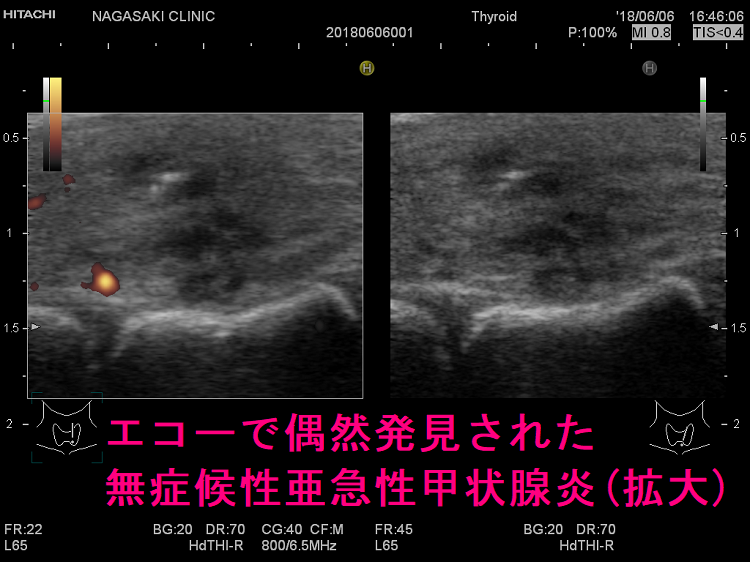

エコーで偶然発見された無症状の亜急性甲状腺炎 超音波(エコー)画像

こんな事が現実にあるのか?と首をひねるケースが時々あります[長崎甲状腺クリニック(大阪)では数年に1回程]。投薬の必要ない甲状腺機能正常橋本病の年次フォローアップ、甲状腺の病気を持つ家族がいるので自分も調べて欲しいなど、亜急性甲状腺炎とは無関係の件で甲状腺超音波(エコー)検査を行うと、偶然、亜急性甲状腺炎らしき低エコー領域が見つかることがあります。低エコー領域は痛みも発熱もなく、1-2か月後には消えてしまいます。

写真で分かる通り低エコー領域が不規則な形で、明らかに無痛性甲状腺炎の炎症巣とは異なります。甲状腺機能も正常で、一般的な項目に異常はありません。